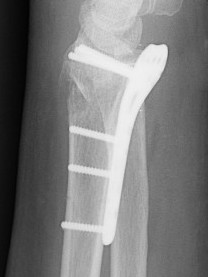

Malunion

www.boneschool.com/distal-radius-fracture-malunion